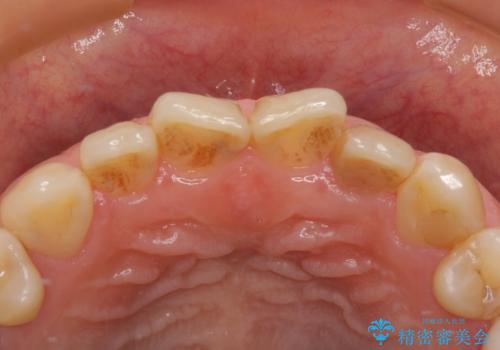

根元がうずく前歯 根管治療とオールセラミック治療

- 前歯に痛みを感じて来院された患者様です。

以前虫歯治療を行った歯が痛み出し、鼻の下を押すと強い痛みを感じていました。

レントゲン写真から、大きくなった根尖病変が認められました。

根管治療を行い、その後オールセラミッククラウンにて補綴治療を行うこととしました。

根管治療後速やかに痛みが消退し、6ヶ月後のレントゲン写真では、根尖部の病変がほぼなくなっていることが分かりました。